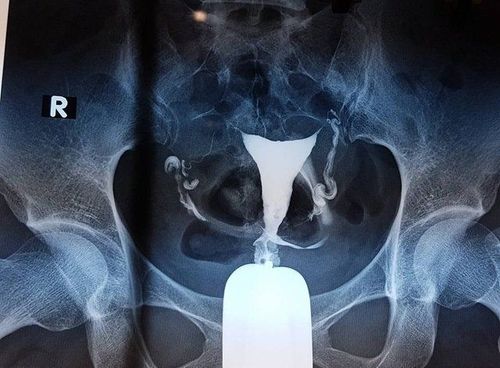

Chụp HSG giúp kiểm tra tình trạng ống dẫn trứng của phụ nữ

Hysterosalpingogram(HSG): Quy trình chụp X-quang này cho phép bác sĩ xem liệu ống dẫn trứng của bạn có bị tắc nghẽn hay không. Nó cũng có thể cho biết liệu cấu trúc của tử cung của bạn có bình thường hay không hoặc liệu bạn có polyp, u xơ, mô sẹo hoặc các bất thường khác ở tử cung có thể ảnh hưởng đến khả năng sinh sản của bạn hay không?

Bác sĩ sẽ tiêm một loại thuốc nhuộm đặc biệt qua cổ tử cung vào tử cung và ống dẫn trứng của bạn và theo dõi chuyển động của nó bằng tia X.